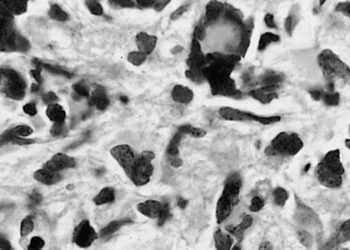

The Scan by 2 Minute Medicine®: Patient Zero: Immunotherapy for Brain Tumors?, Over-the-Counter Birth Control, Florida Supreme Court Deals a Devastating Blow to Abortion Access, Schwarzenegger’s Post-Pacemaker Update on Instagram